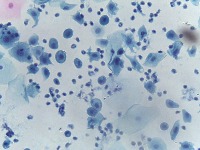

Medical Diagnostics: This model can be used in the healthcare industry to provide high-speed automated analysis of pathology slides, determining whether cells are normal or abnormal, and assisting in diagnosis of various diseases such as cancer.

Scientific Research: Researchers studying cell biology or genetics can use this AI model for their studies on cellular abnormalities and diseases. This can accelerate the onset of breakthroughs in medical science.

Pharmaceutical Applications: Pharmaceutical companies can use this model in drug discovery and development process. By identifying how different medications affect normal and abnormal cells, they can speed up and enhance their research.

Educational Tool: This AI model could serve as a rich educational tool in courses related to biology, medicine and health sciences, helping students to visualize and understand differences between normal and abnormal cells.

Personalized Medicine: This model can be used to analyze patients' cells to create personalized treatment plans. Understanding an individual's cellular structure could help healthcare professionals tailor treatments to the patient's specific needs.